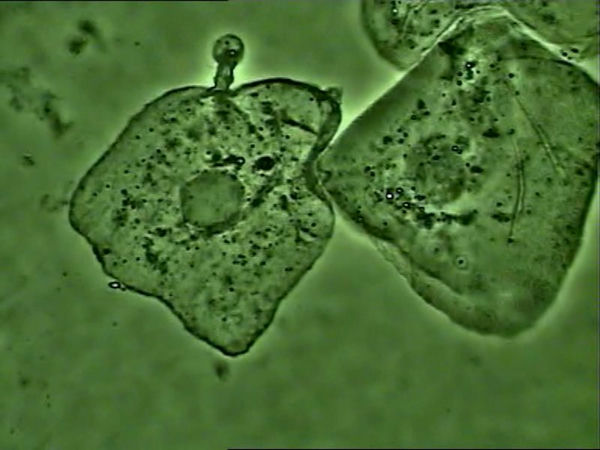

支原體感染的細胞

支原體主要黏附在細胞膜上生存,使用光學顯微鏡高倍相襯觀察,如果看到細胞核周圍大量靜止或布朗運動的小黑點,可以推斷大概率為支原體。